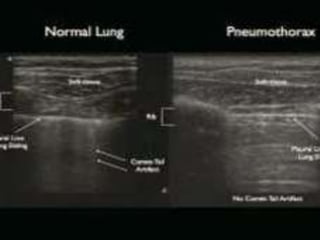

5. Pneumothorax

Chest US may be help in the diagnosis of

pneumothoraces.

Normal parietal and visceral pleura slide over each other

during respiration and a pneumothorax is suspected

when this ‘Gliding sign’ is absent in chest US

A recently published systemic review, chest US had a

sensitivity of 90.0% and a specificity of 98.2% .

The confirmation of lung gliding has a 100% negative

predictive value for the absence of pneumothorax .

The use of M-mode can also objectify the presence or

absence of lung gliding

Pneumothorax

Normal Lung

M-mode for sliding - normal

straight

speckled